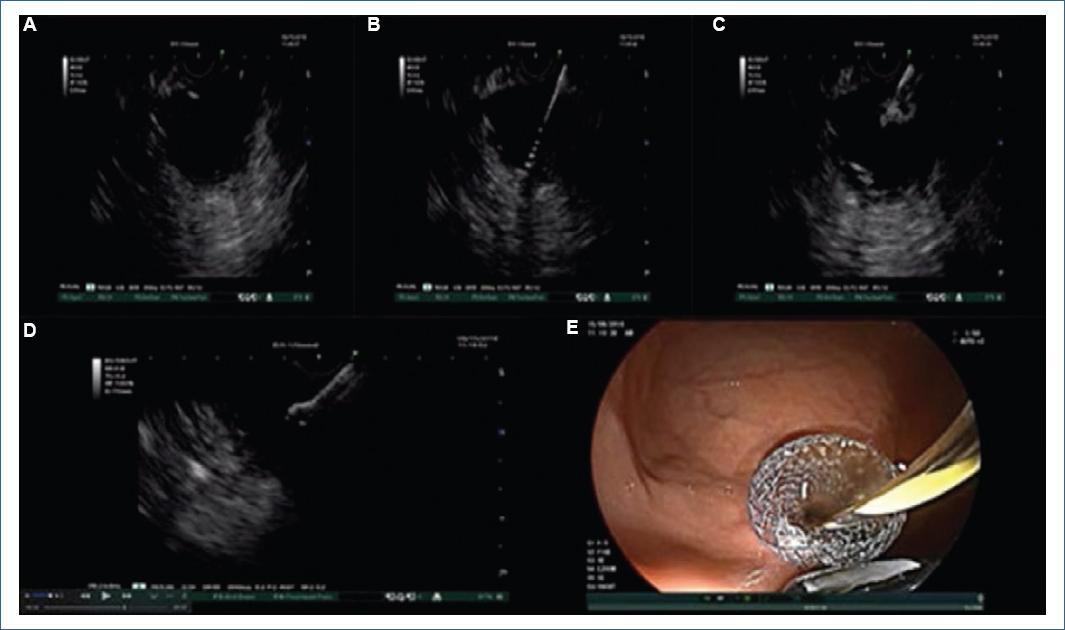

Una vez localizada la necrosis con pared o el pseudoquiste, mediante la realización de USE, se busca una ventana óptima para asegurar una distancia adecuada entre la colección líquida y la luz del tubo digestivo; por lo general la distancia debe de ser menor a 10 mm. Se realiza rastreo con Doppler para asegurar que no se encuentre vasos de gran calibre entre la luz intestinal y la colección. Posteriormente se utiliza una aguja 19 G para realizar una punción de la pared de la cámara gástrica o duodenal a la colección líquida. Posteriormente se inserta una guía hidrofílica 0.035 por la aguja hasta la colección líquida y se retira la aguja, dejando la guía en la colección. Posteriormente se necesita crear una fístula mediante la utilización de un cistostomo y ampliarla con un balón dilatador, posteriormente se procede a colocación de la prótesis ( Figura 1) 11.

Figura 1 Técnica endoscópica; drenaje por ultrasonido endoscópico. A: localización de la colección líquida, evaluación con Doppler de tejidos periféricos. B: acceso a la colección con aguja 19 G e introducción de una guía 0.035. C: creación de fístula con cistostomo y dilatación con un balón dilatador. D: liberación de copa de la prótesis dentro de la colección con guía ultrasonográfica. E: liberación de copa de la prótesis en cámara gástrica.